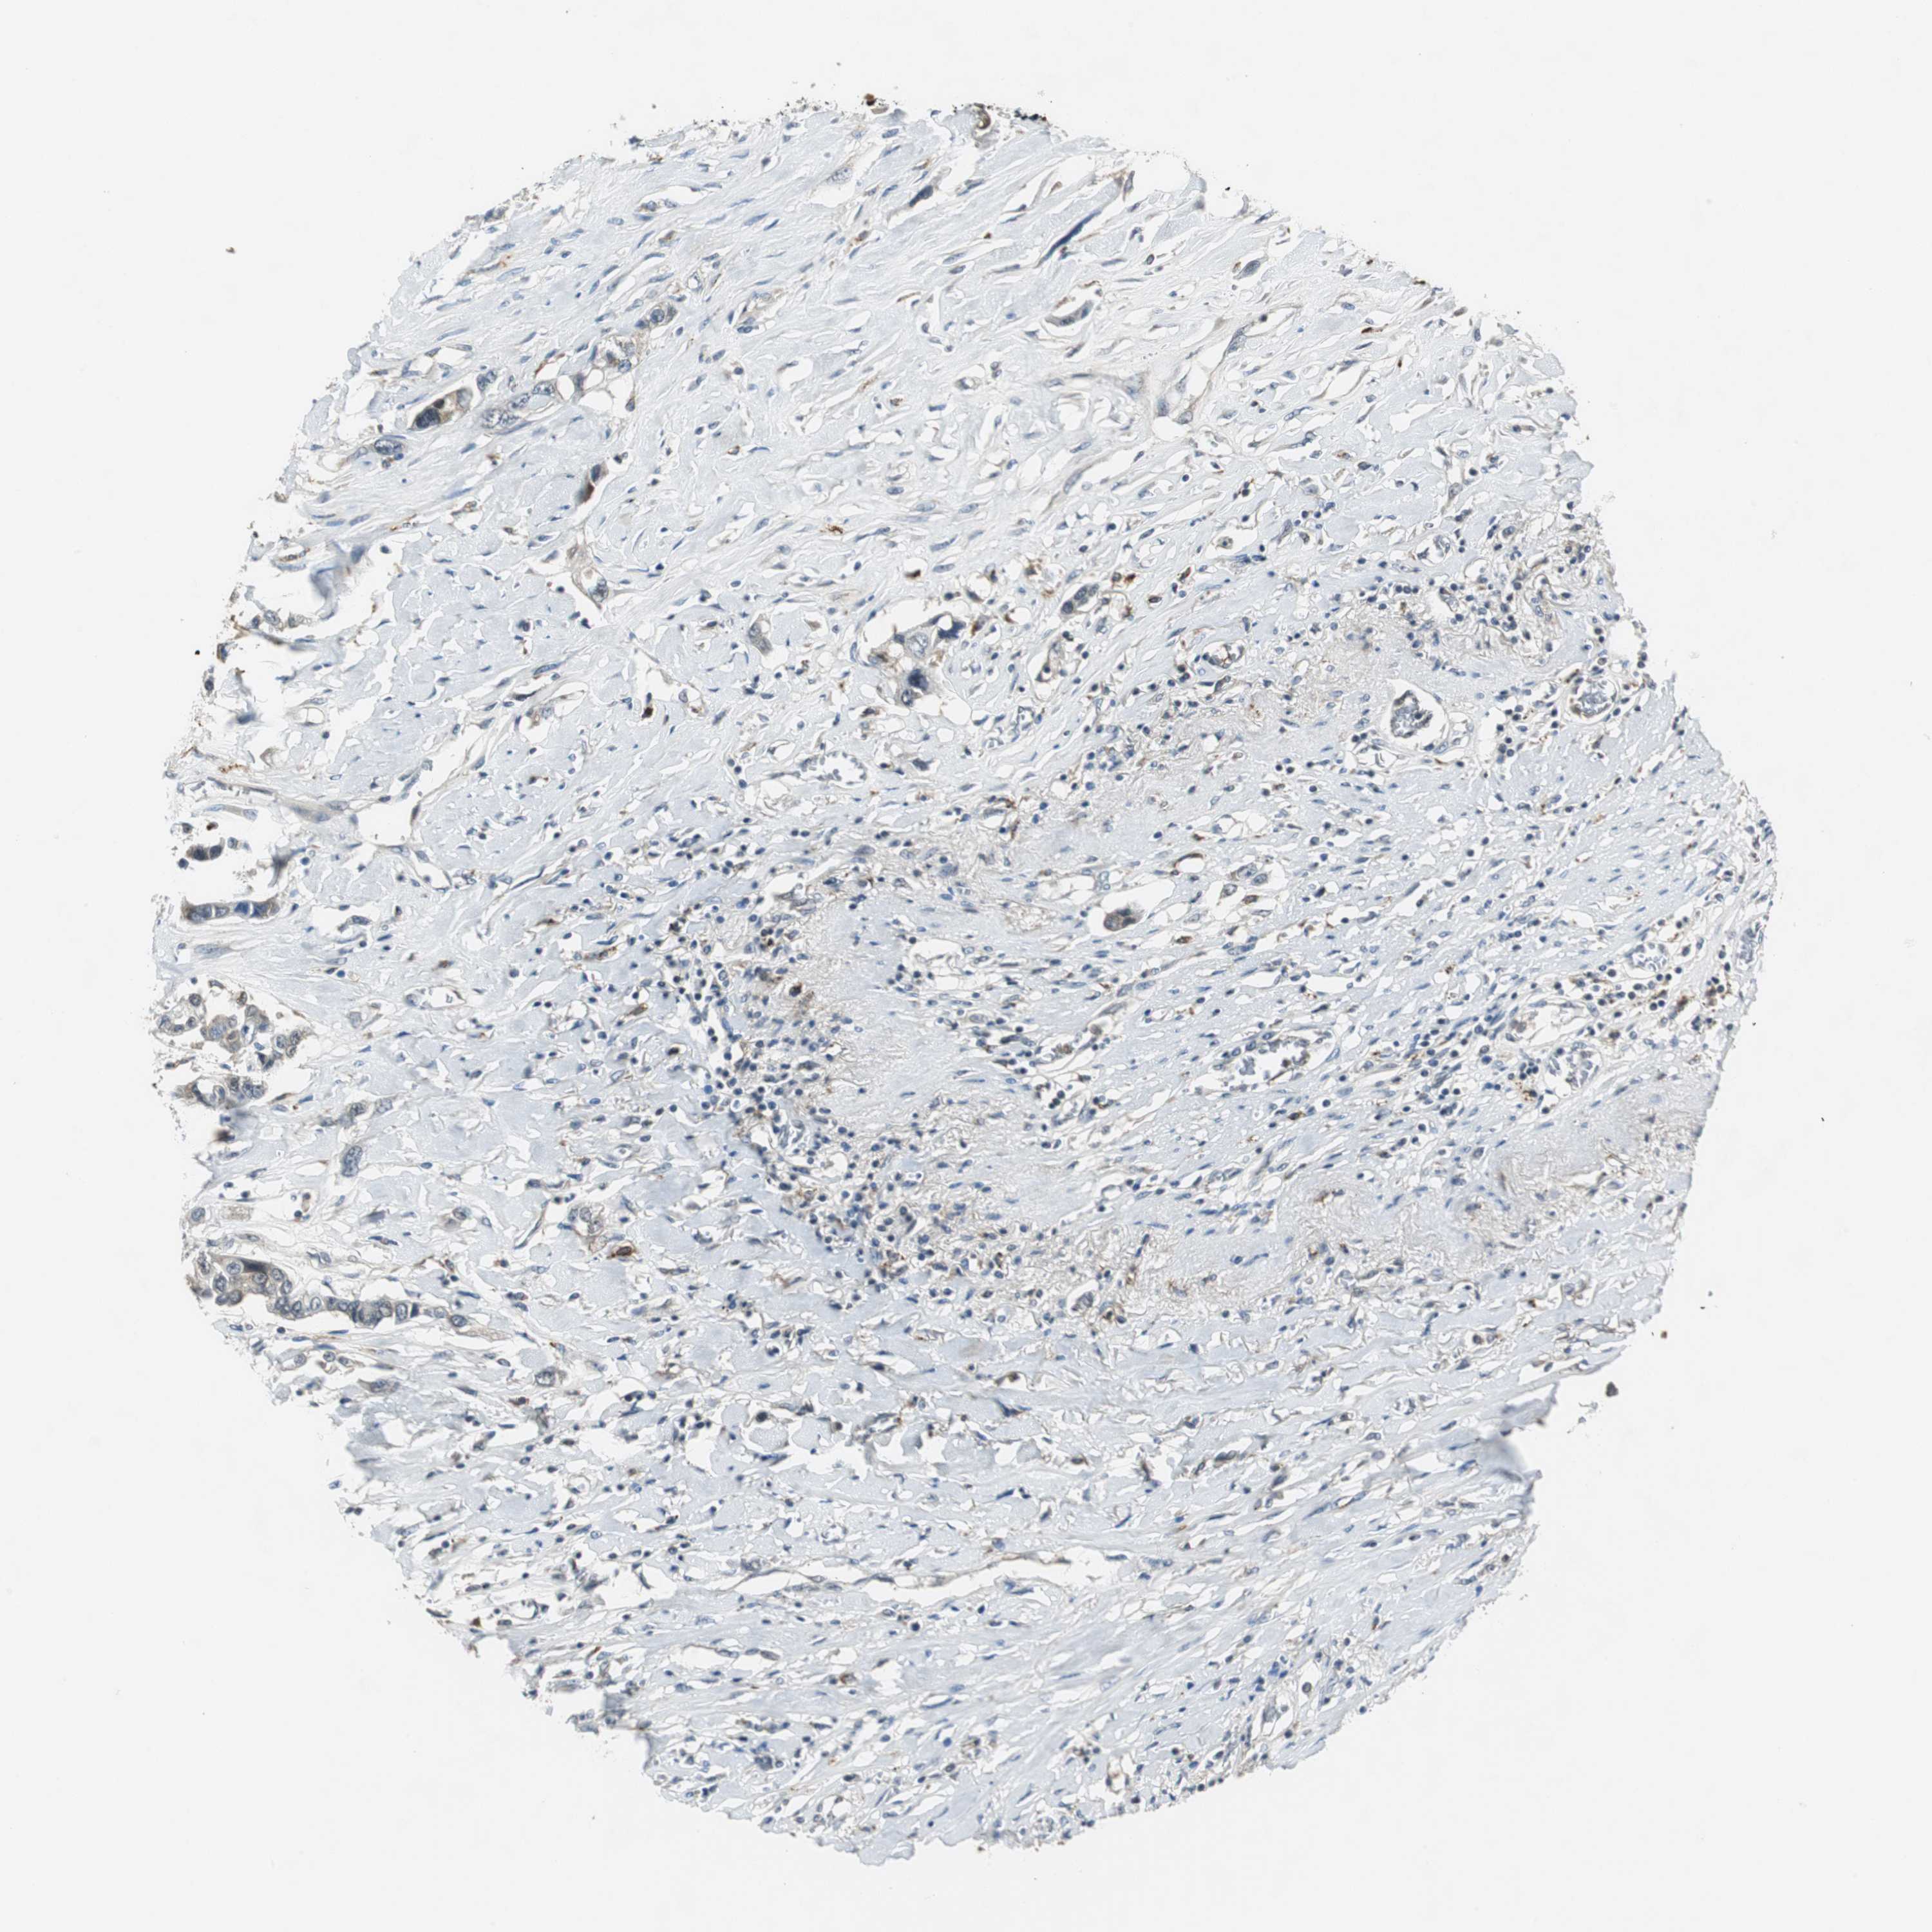

LUNG ADENOCARCINOMA (VALIDATION) - Interactive survival scatter ploti

The Survival Scatter plot shows the clinical status (i.e. dead or alive) for all individuals in the patient cohort, based on the same data that underlies the corresponding Kaplan-Meier plots. Patients that are alive at last time for follow-up are shown in blue and patients who have died during the study are shown in red.

The x-axis shows the expression levels (FPKM) of the investigated gene in the tumor tissue at the time of diagnosis. The y-axis shows the follow-up time after diagnosis (years). Both axes are complimented with kernel density curves demonstrating the data density over the axes. The top density plot shows the expression levels (FPKM) distribution among dead (red) and alive patients (blue). The right density plot shows the data density of the survived years of dead patients with high and low expression levels respectively, stratified using the cutoff indicated by the vertical dashed line through the Survival Scatter plot. This cutoff is automatically defined based on the FPKM cutoff that minimizes the p-score. The cutoff can be changed by dragging the vertical line or by entering a cutoff value in the square labeled "Current cut-off".

Under the Survival Scatter plot the p-score landscape (black curve; left axis) is shown together with dead median separation (red curve; right axis). Dead median separation is the difference in median mRNA expression between patients who have died with high and low expression, respectively. It is calculated as follows: median FPKM expression of dead patients with high expression - median FPKM expression of dead patients with low expression. This is intended to aid the user in visually exploring custom cutoffs and the associated p-scores and dead median separation.

Individual patient data is displayed and can be filtered by clicking on one or more of the category buttons on the top of the page. Categories describing expression level and patient information include: high, low, alive, dead, female, male and tumor stages. The scale of the x-axis can be toggled between linear and log-scale by clicking on the "x log" button. Mouse-over function shows TCGA ID, patient information and mRNA expression (FPKM) for each patient.

& Survival analysisi

Kaplan-Meier plots summarize results from analysis of correlation between mRNA expression level and patient survival. Patients were divided based on level of expression into one of the two groups "low" (under cut off) or "high" (over cut off). X-axis shows time for survival (years) and y-axis shows the probability of survival, where 1.0 corresponds to 100 percent.

NCK1 is not prognostic in Lung Adenocarcinoma (validation)

: 35.54